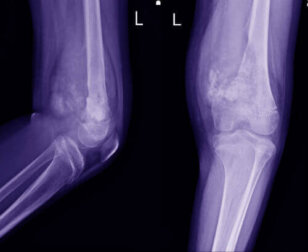

Die Diagnose wird in der Regel auf der Grundlage einer klinischen Befragung und der Krankengeschichte sowie einiger Tests gestellt. Sie beginnt üblicherweise mit Röntgenaufnahmen, die durch ein MRT ergänzt werden. Wenn der Arzt ein Problem feststellt und den Bereich identifiziert, wird er eine Biopsie anordnen.

Nach der Bestätigung der Diagnose ordnet der Arzt eine Computertomographie des Brustkorbs, eine Knochenszintigraphie und manchmal weitere MRT-Untersuchungen an. So kann er eine genauere Diagnose stellen und eine effektivere Behandlung festlegen.